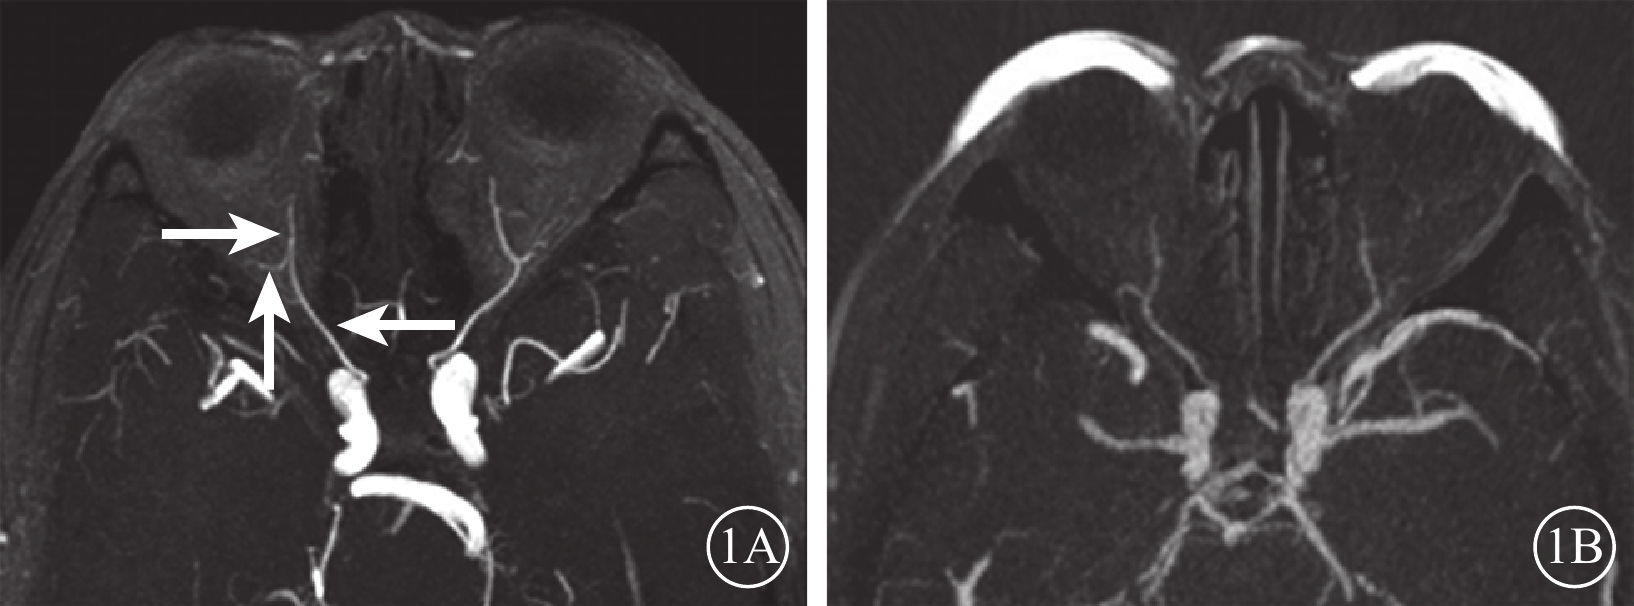

對照組44只眼中,眼動脈MRA 0級41只眼(93.2%);Ⅰ級3只眼(6.8%),其中鼻背動脈和淚腺動脈顯影淺淡2只眼,鼻背動脈顯影中斷1眼。行眼動脈CTA檢查的10只眼均為0級(圖1)。

圖1

對照組受檢者MRA、CTA像。1A. MRA;1B. CTA。雙側眼動脈走行自然,起始部及主干均未見明顯病變及異常中斷,遠端主要分支內側鼻背動脈及外側淚腺動脈走行自然,顯影良好,未見明顯病變及異常中斷(白箭)

圖1

對照組受檢者MRA、CTA像。1A. MRA;1B. CTA。雙側眼動脈走行自然,起始部及主干均未見明顯病變及異常中斷,遠端主要分支內側鼻背動脈及外側淚腺動脈走行自然,顯影良好,未見明顯病變及異常中斷(白箭)

對照組44只眼中,眼動脈MRA 0級41只眼(93.2%);Ⅰ級3只眼(6.8%),其中鼻背動脈和淚腺動脈顯影淺淡2只眼,鼻背動脈顯影中斷1眼。行眼動脈CTA檢查的10只眼均為0級(圖1)。

圖1

對照組受檢者MRA、CTA像。1A. MRA;1B. CTA。雙側眼動脈走行自然,起始部及主干均未見明顯病變及異常中斷,遠端主要分支內側鼻背動脈及外側淚腺動脈走行自然,顯影良好,未見明顯病變及異常中斷(白箭)

圖1

對照組受檢者MRA、CTA像。1A. MRA;1B. CTA。雙側眼動脈走行自然,起始部及主干均未見明顯病變及異常中斷,遠端主要分支內側鼻背動脈及外側淚腺動脈走行自然,顯影良好,未見明顯病變及異常中斷(白箭)